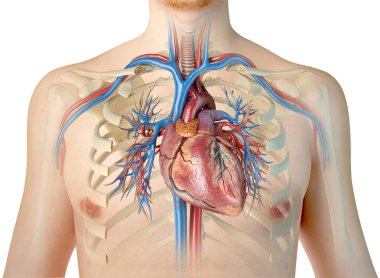

çizim, pulmoner dolaşım

ArkaplankişiİnsanKadınkanİlaçSolunumAvrupa DiliKardiyolojikalpdüzresim çalışmasıAkciğerSistemkemergemiüstünvenanatomiNormalauricletedavülarterAzalanyükselenCavaaortvena cavatorasikaşağıPulmonerventrikül20 30 yıldüz arka planKan damarıSolunum SistemiKan dolaşımıPnömolojiaortik kemerinen aortPulmoner dolaşımtorasik aortyükselen aortaPulmoner arterBenzer İçerikler